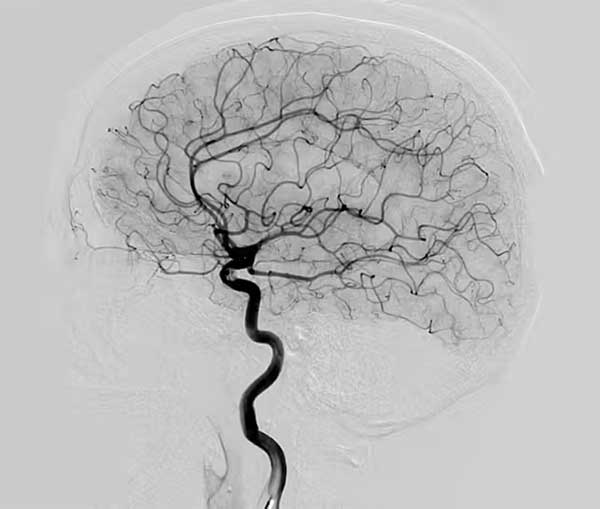

Role of Angiography Before Angioplasty

Angiography is an important diagnostic procedure used to visualize blood vessels and detect blockages in coronary arteries.

This test helps the Best Cardiologist in Mumbai determine the exact location and severity of artery blockage before recommending Angioplasty Surgery in Mumbai.

Cardiac Angiography is one of the most effective procedures used to examine blood vessels and identify coronary artery disease.